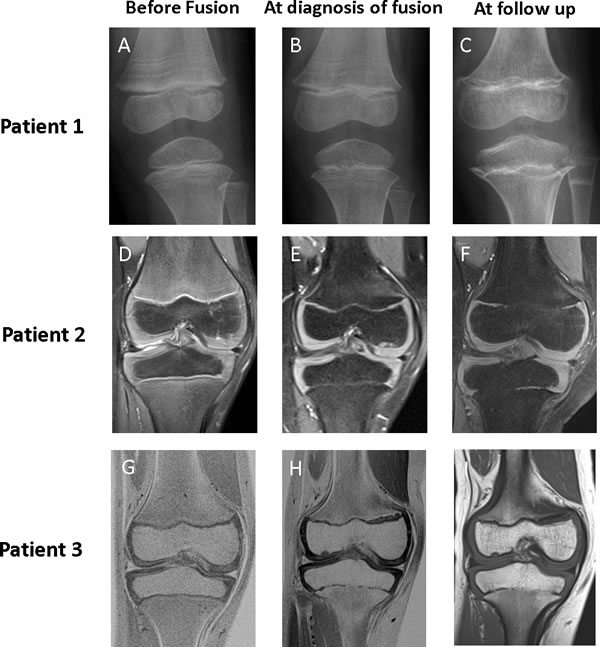

Figure 1: Imaging of knee in patients 1, 2, and 3 before fusion, at diagnosis of fusion, and at follow up. Baseline imaging (Panels A, D, and G) show patent physes in all patients at the start of vismodegib therapy. In patient 1, physeal fusions were initially more pronounced in the proximal tibia, incomplete in the distal femur, and absent in the proximal fibula (Panel B). Follow-up radiography 17 months after stopping therapy (Panel C) showed progression of fusions in all physes and development of abnormal metaphyseal sclerosis. In patients 2 and 3, MRI showed that the initial identification of fusion was subtle, with the development of small bridging fusions at the completion of 12 cycles of vismodegib therapy (Panels E and H). Over time, these bridges widened to occupy more of the physeal stripe, as revealed by the MRI taken 6 months after the completion of vismodegib therapy (Panels F and I).

This 5-year-old white female was recently reported to have premature physeal closure after completing 5 cycles of vismodegib. [9] She was diagnosed with SHH-MB at 2 years of age and treated in a St. Jude institutional protocol aimed at reducing radiation exposure in young children with newly diagnosed brain tumors (NCT00602667). At disease relapse, the patient was taken off protocol therapy and the risks and benefits of additional treatment options such as salvage CSI, intravenous chemotherapy, and vismodegib were discussed with her family. Vismodegib therapy was chosen and informed consent obtained. Constrained by the pill strength of 150 mg, the dose approximated 250 mg/m2. After 3 months of therapy, magnetic resonance imaging (MRI) showed a near-complete radiographic response and treatment was continued. Toward the end of cycle 5, she complained of bilateral lower extremity pain severe enough to wake her from sleep. A knee X-ray revealed incomplete centralized closure of bilateral proximal tibial and distal femoral physes, which was absent from findings of the knee X-ray taken 4 months earlier (Figure 1). MRI of the brain and spine revealed disease recurrence with leptomeningeal spread. Therefore, vismodegib therapy was discontinued.

An 8-year-old black female was diagnosed with SHH-MB at 5 years of age. Her medical history was remarkable for congenital bilateral radial and ulnar synostoses and a family history of medulloblastoma in both her father and paternal aunt. Fluorescence in situ hybridization (FISH) analysis revealed hemizygous loss of PTCH1 in tumor cells; however, a PTCH1 abnormality was not detected upon germline testing. Additional genetic testing to evaluate for other predispositions was offered but declined by the family. Nevertheless, because of high clinical suspicion for NBCCS and resulting heightened sensitivity to ionizing radiation, CSI was omitted from therapy. Consequently, she received SJMB12 protocol therapy with whole posterior fossa radiation instead of CSI, adjuvant chemotherapy, and 12 cycles of vismodegib (188 mg/m2/dose). After 6 cycles of vismodegib, MRI of knees showed normal and patent physes. However, after 12 cycles, she had central bony bridging across physes of tibiae, fibulae, and femora. Despite stopping therapy, subsequent imaging revealed progression of central to peripheral closure (Figure 1).

A 9-year-old white male was diagnosed at age 6 with desmoplastic/nodular variant medulloblastoma of the SHH subgroup. FISH analysis revealed hemizygous loss of PTCH1 in tumor cells. He was enrolled in SJMB12 and received 12 cycles of vismodegib (167 mg/m2/dose). Screening MRIs of the right knee at start and after 6 cycles of vismodegib revealed normal patent physes. MRI of the same knee after 12 cycles showed early central fusion of the proximal tibial physis. Within 6 months, this physis became progressively and abnormally fused, predominantly in central and medial portions (Figure 1). A partially fused proximal femur physis was also observed with an advanced bone age of 12.5 years.